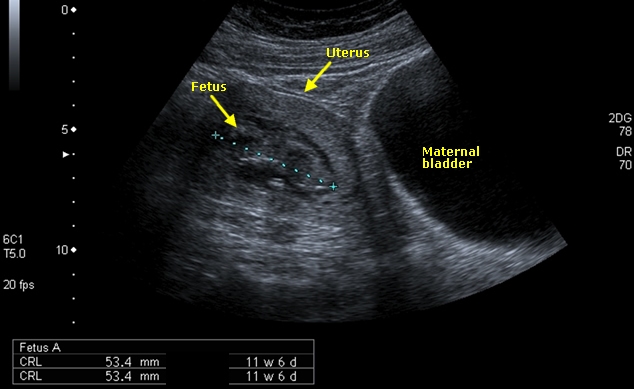

This scan has been performed transabdominally. Detail of the baby is not as clear but we can still see the head and body.

The uterus now extends above the bladder because it has enlarged and can probably be felt just above the bones of the pelvis. The bladder is now less useful for seeing the baby but remains important to look at the placenta. We shall cover this in a later session.